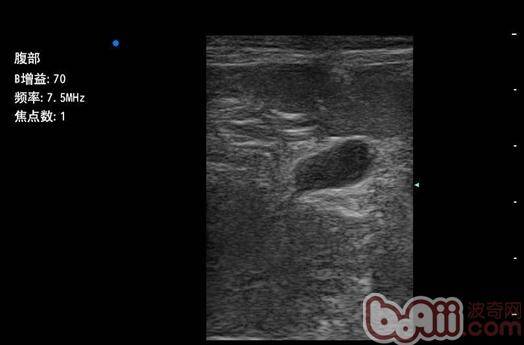

• 犬猫子宫蒂蓄脓症与病例分享

犬猫子宫蒂蓄脓症与病例分享

犬猫绝育手术概况雌性犬猫的绝育手术应该是兽医临床门诊中最常见的手术之一,也是兽医的基础技能,是手术室主要的病例组成。国内外一直有人在研究非手术方法对猫狗实施绝育或者阉割,但是非常遗憾,到目前为止仍然没